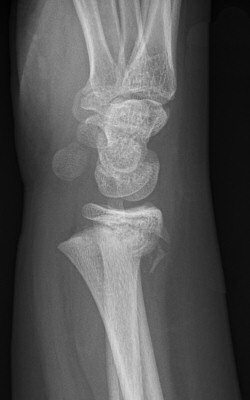

Dorsalbockad distal radiusfyseolys Salter-Harris typ 2 före och efter reposition